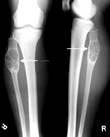

ХРОНИЧЕСКИЙ ПЕРВИЧНО-СКЛЕРОЗИРУЮЩИЙ| ОСТЕОМИЕЛИТ| ГАРРЕ|: начало первично-хроническое, появляется отек в мягких тканях (инфильтрация мышц), ограничение подвижности в соседних суставах. Рентгенологически: остеосклероз, эбурнеация| (деструктивных очагов, полостей, секвестров нет) и гиперостоз|.

Рис..16. Первично-склерозирующий остеомиелит| Гарре.